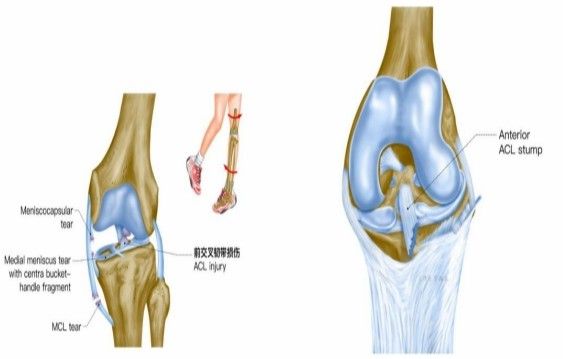

歐洲杯預(yù)選賽小組賽中,被譽為“歐洲金童”年僅20歲的運動員加維,右膝交叉韌帶撕裂,面臨賽季報銷+無緣歐洲杯的痛苦。在運動損傷中,“韌帶撕裂”是一個出現(xiàn)頻率非常高的詞,無論是運動員或者是普通人,在生活和運動中都可能會遭遇“韌帶撕裂。”

我院骨科三病區(qū)近期收治了4名膝關(guān)節(jié)交叉韌帶損傷患者。25歲的齊先生,因打籃球時不慎扭傷左膝,致右膝腫痛,遂來我院治療;30歲趙先生酷愛足球,扭傷右膝關(guān)節(jié)來我院就診;50歲的張先生、42歲劉先生因騎車滑倒摔傷、膝關(guān)節(jié)腫痛不適、活動受限,收治入院。骨科三病區(qū)李鵬主任團隊詳細查體以及完善影像學檢查后進行診斷:幾位患者共同診斷均有“前交叉韌帶損傷”,不同程度合并有“半月板損傷”、“股骨軟骨損傷”、“內(nèi)側(cè)副韌帶斷裂”。

致傷機制

單純前交叉韌帶損傷可發(fā)生于非負重條件下膝強力過伸時(如用力踢時未遇到抵抗),或小腿固定、暴力使股骨向后時。單純前交叉韌帶損傷少見,多合并脛側(cè)副韌帶、半月板的損傷,此三結(jié)構(gòu)的復合傷在膝部韌帶損傷中最為常見(占52%)。損傷多發(fā)生于韌帶中部(占 72%),少數(shù)發(fā)生于股骨附著點撕脫骨折 (18%)或脛骨附著點撕脫骨折(4%)。損傷后關(guān)節(jié)內(nèi)出血、疼痛、活動受限、前抽屜試驗陽性。